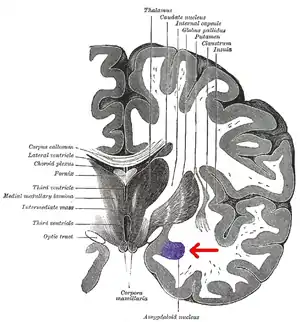

Basolateral amygdala

The basolateral amygdala (BLA), or basolateral complex, consists of the lateral, basal and accessory-basal nuclei of the amygdala. The lateral nuclei receives the majority of sensory information, which arrives directly from the temporal lobe structures, including the hippocampus and primary auditory cortex. The information is then processed by the basolateral complex and is sent as output to the central nucleus of the amygdala. This is how most emotional arousal is formed in mammals.[1]

The amygdala has several different nuclei and internal pathways; the basolateral complex (or basolateral amygdala), the central nucleus, and the cortical nucleus are the most well-known. Each of these has a unique function and purpose within the amygdala.